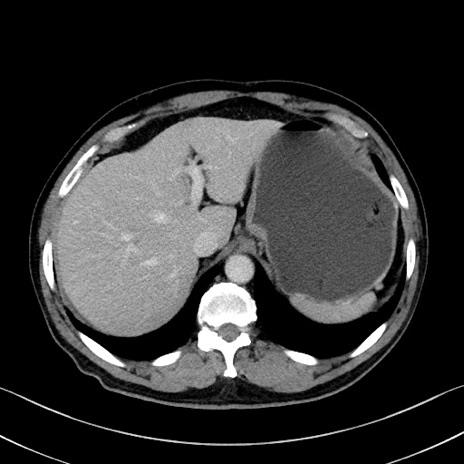

症例35(横断像)

【症例】70歳代 男性

【主訴】腹部膨満、嘔吐

【現病歴】昨日より腹部膨満感出現。本日増悪し、仙痛出現。嘔吐あり、受診。

【既往歴】糖尿病、胆摘後

【身体所見】BP 149/80mmHg、HR 74/min、BT 35.9℃、腹部:膨満、軟、圧痛なし。腸雑音減弱あり。上腹部正中切開瘢痕あり。

【データ】WBC 13500、CRP 1.72